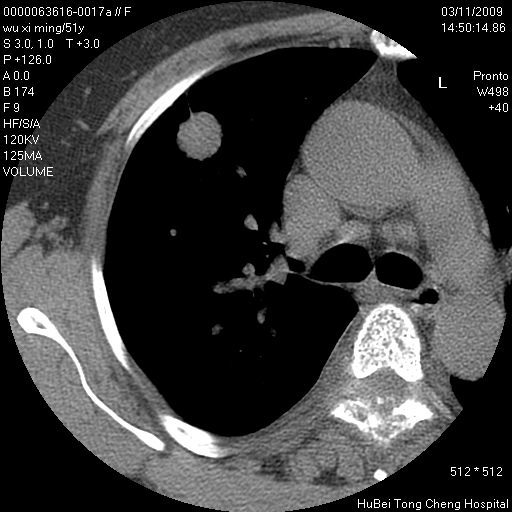

患者 女,51岁。因“胆囊炎,胆囊结石”,行常规术前胸部x线检查发现:右上肺结节病灶,建议行进一步检查。患者无咳嗽、咳痰及咯血等呼吸道症状,近期出现背部疼痛不适。

胸部ct轴位平扫(层厚10mm,螺距1.5,重建间隔10mm;部分层面:层厚3mm,螺距1.0,重建间隔3mm),图像如下:

右肺周围型肺癌伴肺内转移信胸椎转移

支持--右肺周围型肺癌---胸椎转移

有周围性肺癌胸椎转移

右肺周围型肺癌伴肺内转移及胸椎转移。已无手术机会。